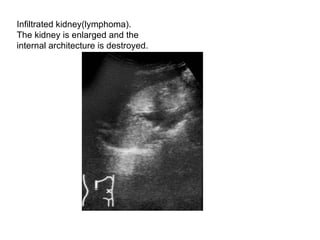

Infiltrated kidney(lymphoma).  The kidney is enlarged and the  internal architecture is destroyed.